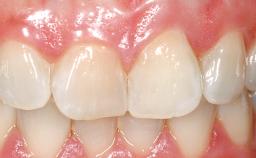

Late Placement of an Implant in a Maxillary Left Central Incisor Site

On examination, the patient had a low lip line and only displayed the coronal half of the anterior teeth when smiling.

The crown of tooth 21 was splinted to the adjacent teeth with composite resin, and the gingiva was inflamed.